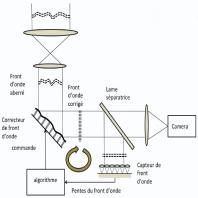

- eFig. 9-10 - Principe de fonctionnement de l'imagerie par optique adaptative